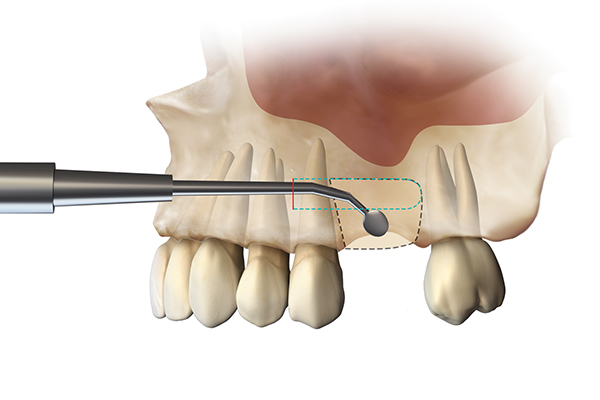

Because recession was already present on tooth No. 5, the scope of the SMART procedure was extended to horizontally augment adjacent areas that exhibited dehiscences and thin buccal plates (Figure 16). The augmented areas evident in Figure 16 (which can be compared to the preoperative imaging in Figure 4) were accomplished using two remote incisions. It must be emphasized, however, that this procedure may be technique sensitive, and predictable outcomes require training and experience. Unlike lateral subperiosteal techniques, the SMART method is based on the development of a laparoscopic tunnel from a remote incision to access the graft site. A subperiosteal pouch is subsequently created to confine the biomaterial particles (Figure 17 and Figure 18). This approach ensures that surgical trauma to the subperiosteum and the associated inflammatory reaction do not interfere with healing of the bone graft. Specially designed instruments are required to control the elevation of the periosteum, reach the graft site, and develop the subperiosteal pouch.